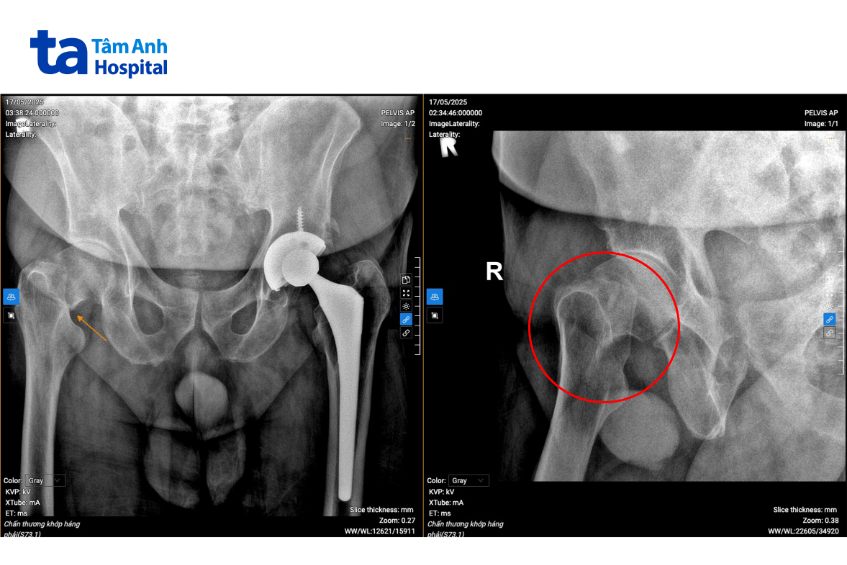

Ông Paul được đưa đến Bệnh viện Đa khoa Tâm Anh TP HCM trong tình trạng đau rất nhiều và gần như không thể cử động chân phải sau khi té ngã. Ngay khi nhập viện, người bệnh lập tức được đưa đi chụp X-quang và thực hiện các xét nghiệm cần thiết. Kết quả cho thấy ông bị gãy cổ xương đùi phải, kèm các bệnh lý nền như tăng huyết áp, thiếu máu cơ tim, tiểu đường.

ThS.BS.CKI Hồ Văn Duy Ân, Trung tâm Chấn thương Chỉnh hình, Bệnh viện Đa khoa Tâm Anh TP HCM, cho biết đối với gãy xương ở vùng háng ở người lớn tuổi mắc nhiều bệnh nền như ông Paul, nếu điều trị chậm trễ hoặc chỉ điều trị bảo tồn, nguy cơ tử vong lên đến 20 – 30% trong năm đầu tiên. Các bác sĩ hội chẩn khẩn để lên kế hoạch thay khớp háng cho ông Paul theo chương trình mổ cấp cứu gãy xương trong 24 giờ, phối hợp nhiều chuyên khoa.

Sau khoảng 13 giờ từ lúc nhập viện, ông Paul được chỉ định thay khớp háng bán phần. Phương pháp này giúp bảo tồn xương và mô mềm xung quanh khớp, người bệnh ít đau và phục hồi nhanh hơn, giảm nguy cơ biến chứng sau mổ. Thay khớp háng bán phần thường được chỉ định cho những trường hợp người cao tuổi gãy cổ xương đùi di lệch nhiều hoặc có các bệnh lý nội khoa, không đảm bảo sức khỏe để thực hiện các ca mổ dài và phức tạp như ông Paul.

Trong quá trình phẫu thuật, bác sĩ giữ lại phần xương khỏe mạnh và nguyên vẹn, loại bỏ xương và sụn hư hỏng ở chỏm xương đùi đã bị gãy. Sau đó thay thế bằng chỏm xương đùi nhân tạo. Ca phẫu thuật kéo dài 1 giờ. Tổng thời gian từ khi người bệnh nhập viện đến khi hoàn tất phẫu thuật diễn ra trong chưa đến 15 giờ.